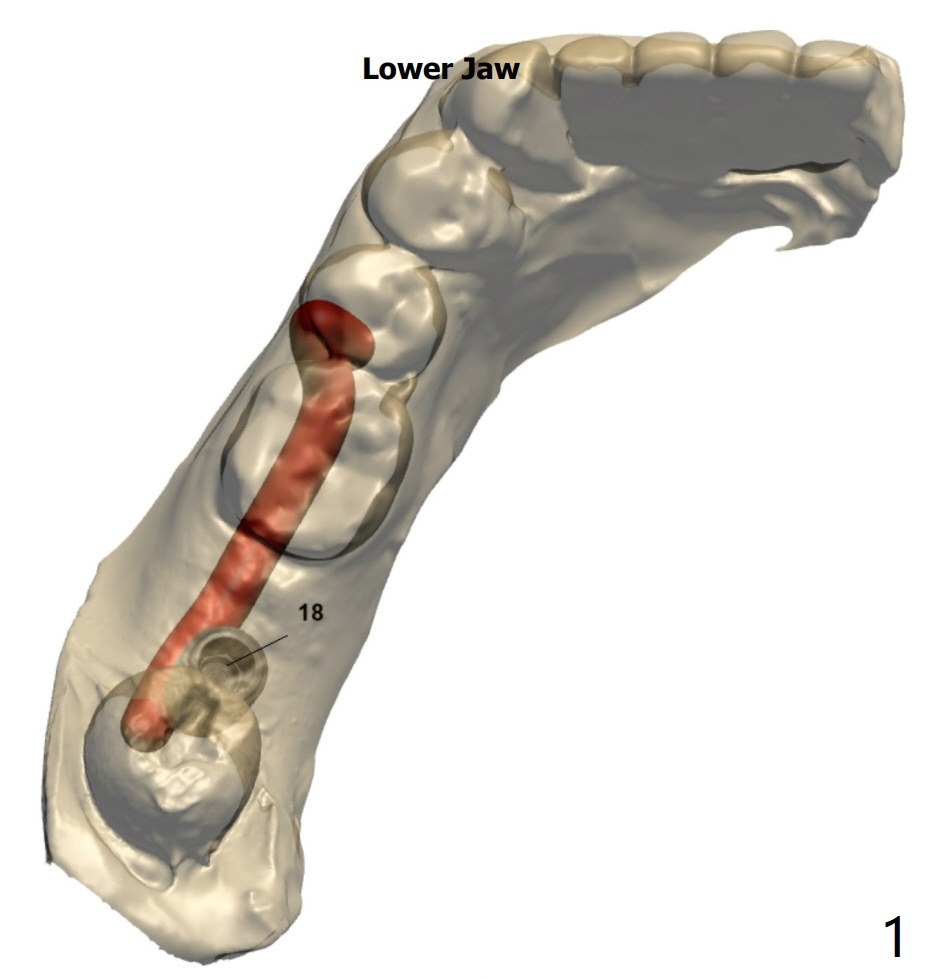

植体周围骨缺损

完成钻洞后,检查近中颊侧缺损,必要时植骨,收集钻头上的骨粉